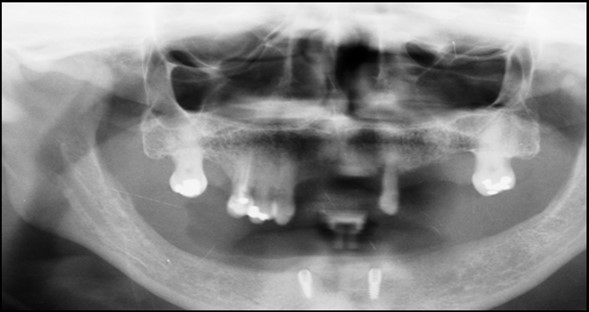

A 63 year old male patient came to our Aesthetics Dental Clinic ,Athens, Greece with the chief complaint of loose fitting lower denture with difficulty in mastication and speech. On examination, patient had resorbed alveolar ridge which lead to inadequate retention of the lower denture prosthesis and patient is known to be a previous denture wearer for past 1 year. The Orthopantomograph findings showed the presence of sufficient bone height and width (Figure 1), with dense cortical bone surrounded by dense trabecular bone. Thus implant supported overdenture was planned with two implants along with independent ball type attachments.

Figure 1.First Visit Pre-operative radiograph

First Visit Pre-operative radiograph

Figure 5.a,b. Post-insertion radiographics in the mandibular area right,left,

a,b. Post-insertion radiographics  in the mandibular area right,left,

Figure 6.Panoramic radiograph after the insertion of two implants

Panoramic radiograph after the insertion of two                 implants